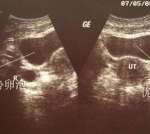

如果有生育的要求,最好用排卵试纸监测排卵,或者做B超监测排卵,在排卵期性生活,这样怀孕的几率比较大,但是并没有什么因素,能够决定胎儿的性别,而且在怀孕期间,我国也有规定,不允许鉴别胎儿的性别。

正常卵泡的直径达到18至25mm会排出。不过也因人而异,不同人卵泡多大排出是不一样的,在正常范围内即可。回归上面的问题,根据卵泡的大小来判断生男生女是不科学的,可以排除这个因素,因为卵泡的大小和生男孩女孩没有没有任何关系,如果卵泡不能发育良好,就不能排出发育正常的卵子或者排出的是质量不好的卵子,会影响正常受孕,所以只有发育成熟的卵泡,其功能才会齐全。